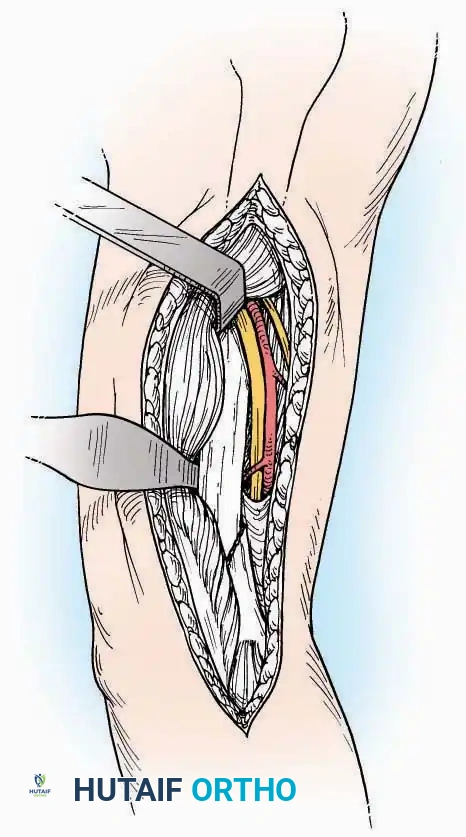

Anterior Approach

Indications: Total ankle arthroplasty (TAA), anterior ankle arthrodesis, and excision of anterior tibial/talar osteophytes (anterior impingement).

Surgical Technique:

* Incision: Make a 10 to 15 cm longitudinal incision over the anterior aspect of the ankle, centered exactly midway between the medial and lateral malleoli.

* Superficial Dissection: Incise the superficial fascia. Identify and protect the superficial peroneal nerve branches laterally and the saphenous nerve medially.

* Internervous Plane: The deep dissection exploits the plane between the Extensor Hallucis Longus (EHL) tendon (innervated by the deep peroneal nerve) and the Extensor Digitorum Longus (EDL) tendons (also innervated by the deep peroneal nerve).

* Neurovascular Bundle: Incise the extensor retinaculum. Carefully identify the anterior tibial artery and the deep peroneal nerve, which typically lie between the EHL and EDL, or directly deep to the EHL. Retract the neurovascular bundle laterally with the EDL, or medially with the EHL, depending on the specific anatomical variant encountered (lateral retraction is most common).

* Capsulotomy: Incise the anterior joint capsule longitudinally. Elevate the capsule subperiosteally from the anterior tibia and the talar neck to expose the entire tibiotalar articulation.